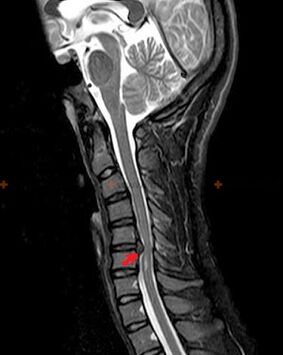

The following research methods are used to diagnose osteochondrosis: radiography (preferably with functional tests), MSCT and MRI.The latter examination is the most advantageous, as it allows a very clear visualization of the state of the intervertebral structures.

The presence of the changes described above, as well as changes in the structure of the intervertebral disc detected by MSCT and MRI, serve as a reliable sign that confirms the presence of osteochondrosis.